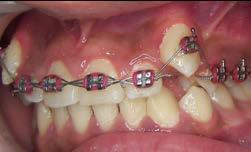

Tratamiento de caninos retenidos superiores en paciente en crecimiento con clase II división 2. Reporte de caso clínico

Caso clínico

Los caninos retenidos constituyen una alteración eruptiva frecuente, con mayor prevalencia en la arcada superior. Su etiología es multifactorial y puede interferir con el trayecto normal de erupción, comprometiendo la oclusión y la estética.

Objetivo: Corregir una maloclusión Clase II división 2 mediante tratamiento ortodóntico en un paciente en crecimiento con ambos caninos superiores retenidos. Metodología: Se presenta el caso de un paciente masculino de 12 años, en dentición permanente, con perfil convexo, patrón dolicofacial y Clase II esquelética. Se realizó tratamiento ortodóntico sin extracciones. Para la tracción y alineación de los caninos retenidos se emplearon resortes abiertos (open coil springs) para la creación de espacio. Resultados: